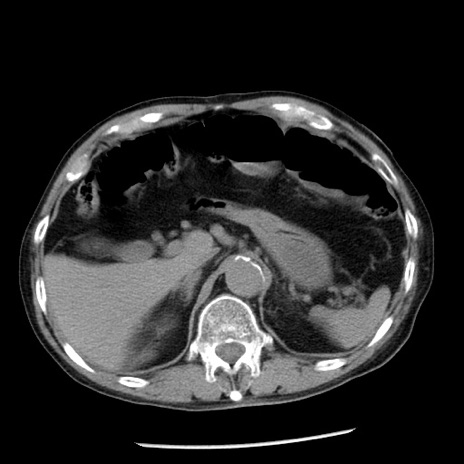

症例26(横断像)

【症例】80歳代男性

【主訴】嘔吐

【現病歴】昨晩2回嘔吐あり、今朝になっても嘔吐あり。来院。

【既往歴】胃潰瘍

【身体所見】意識清明、BT 37.6℃、BP 166/95mmHg、HR 100bpm、SpO2 97%、腹部:平坦・軟、腸蠕動音聴取良好、圧痛なし。

【データ】WBC 21900、CRP 1.46